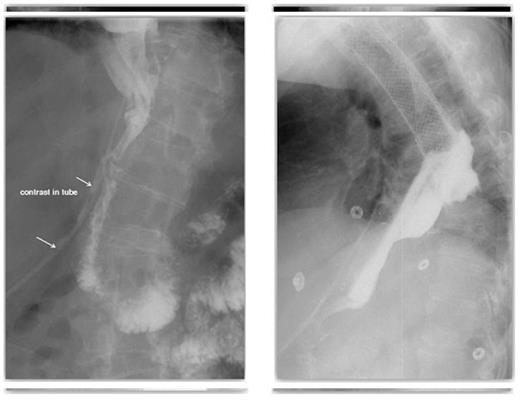

Follow up CT, with contrast both orally and through the T-tube, showed no evidence of ongoing leak from the pyloroplasty. The flanged T–tube satisfactorily plugged the hole through the anterior wall of the pyloroplasty, best demonstrated in the lateral decubitus position (Figures 7 and 8).

A follow-up CT demonstrating no evidence of on-going leak from the pyloroplasty & A follow-up CT demonstrating the flanged T-tube satisfactorily plugging the hole through the anterior wall of the pyloroplasty